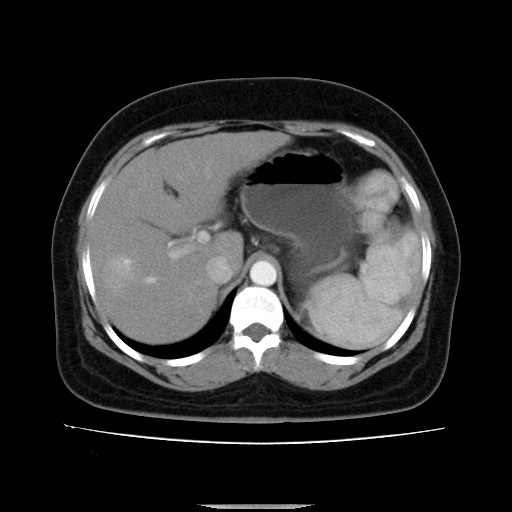

标题: CT14225:女性46岁。当地B超示肝内占位,来我院作CT检查。请 [打印本页]

标题: CT14225:女性46岁。当地B超示肝内占位,来我院作CT检查。请

速升速降,支持肝癌.脾体积增大,形态欠规整,请询问病史是否做过脾动脉栓塞.

速升速降,支持肝癌可能。

快进快出,符合肝癌表现-----------

肝内结节强化特点符合原发性肝癌表现,脾脏改变考虑为增大及先天发育所致。

动脉期病原灶明显强化高于肝密度且中央有无强化区,静脉期强化程度下降明显,延迟低于肝密度,考虑肝腺瘤可能性大,

此患者虽然符合快进的特点,却不符合快出的特点,因为门脉期几乎是等密度,不符合肝癌的增强表现,所以我考虑肝局灶性结节增生可能性大